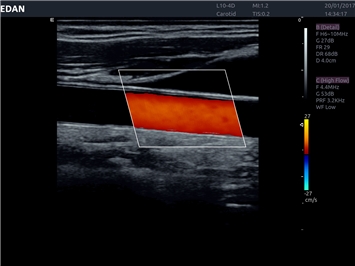

• Сосудистой диагностики

Цветовой допплер:

Да

Дуплексное сканирование: